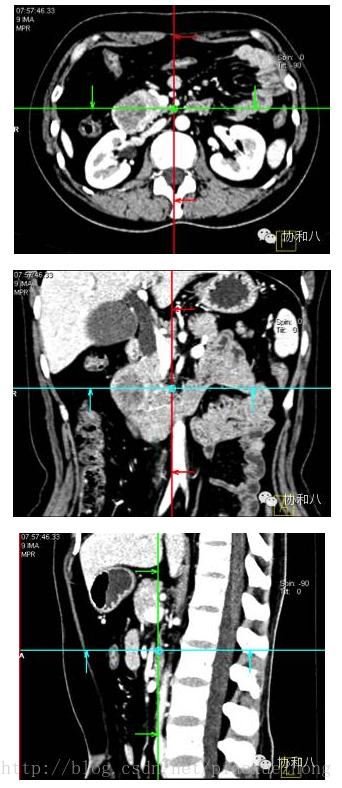

多层面重建(MPR)

多层面重建是最基本的“三维”重建成像方法,是二维的图像序列,和我们最熟悉的轴位图像是一个“家族”的。

MPR适用于任一平面的结构成像,以任意角度观察正常组织器官或病变,可以显示腔性结构的横截面以观察腔隙的狭窄程度、评价血管受侵情况、真实地反映器官间的位置关系等。